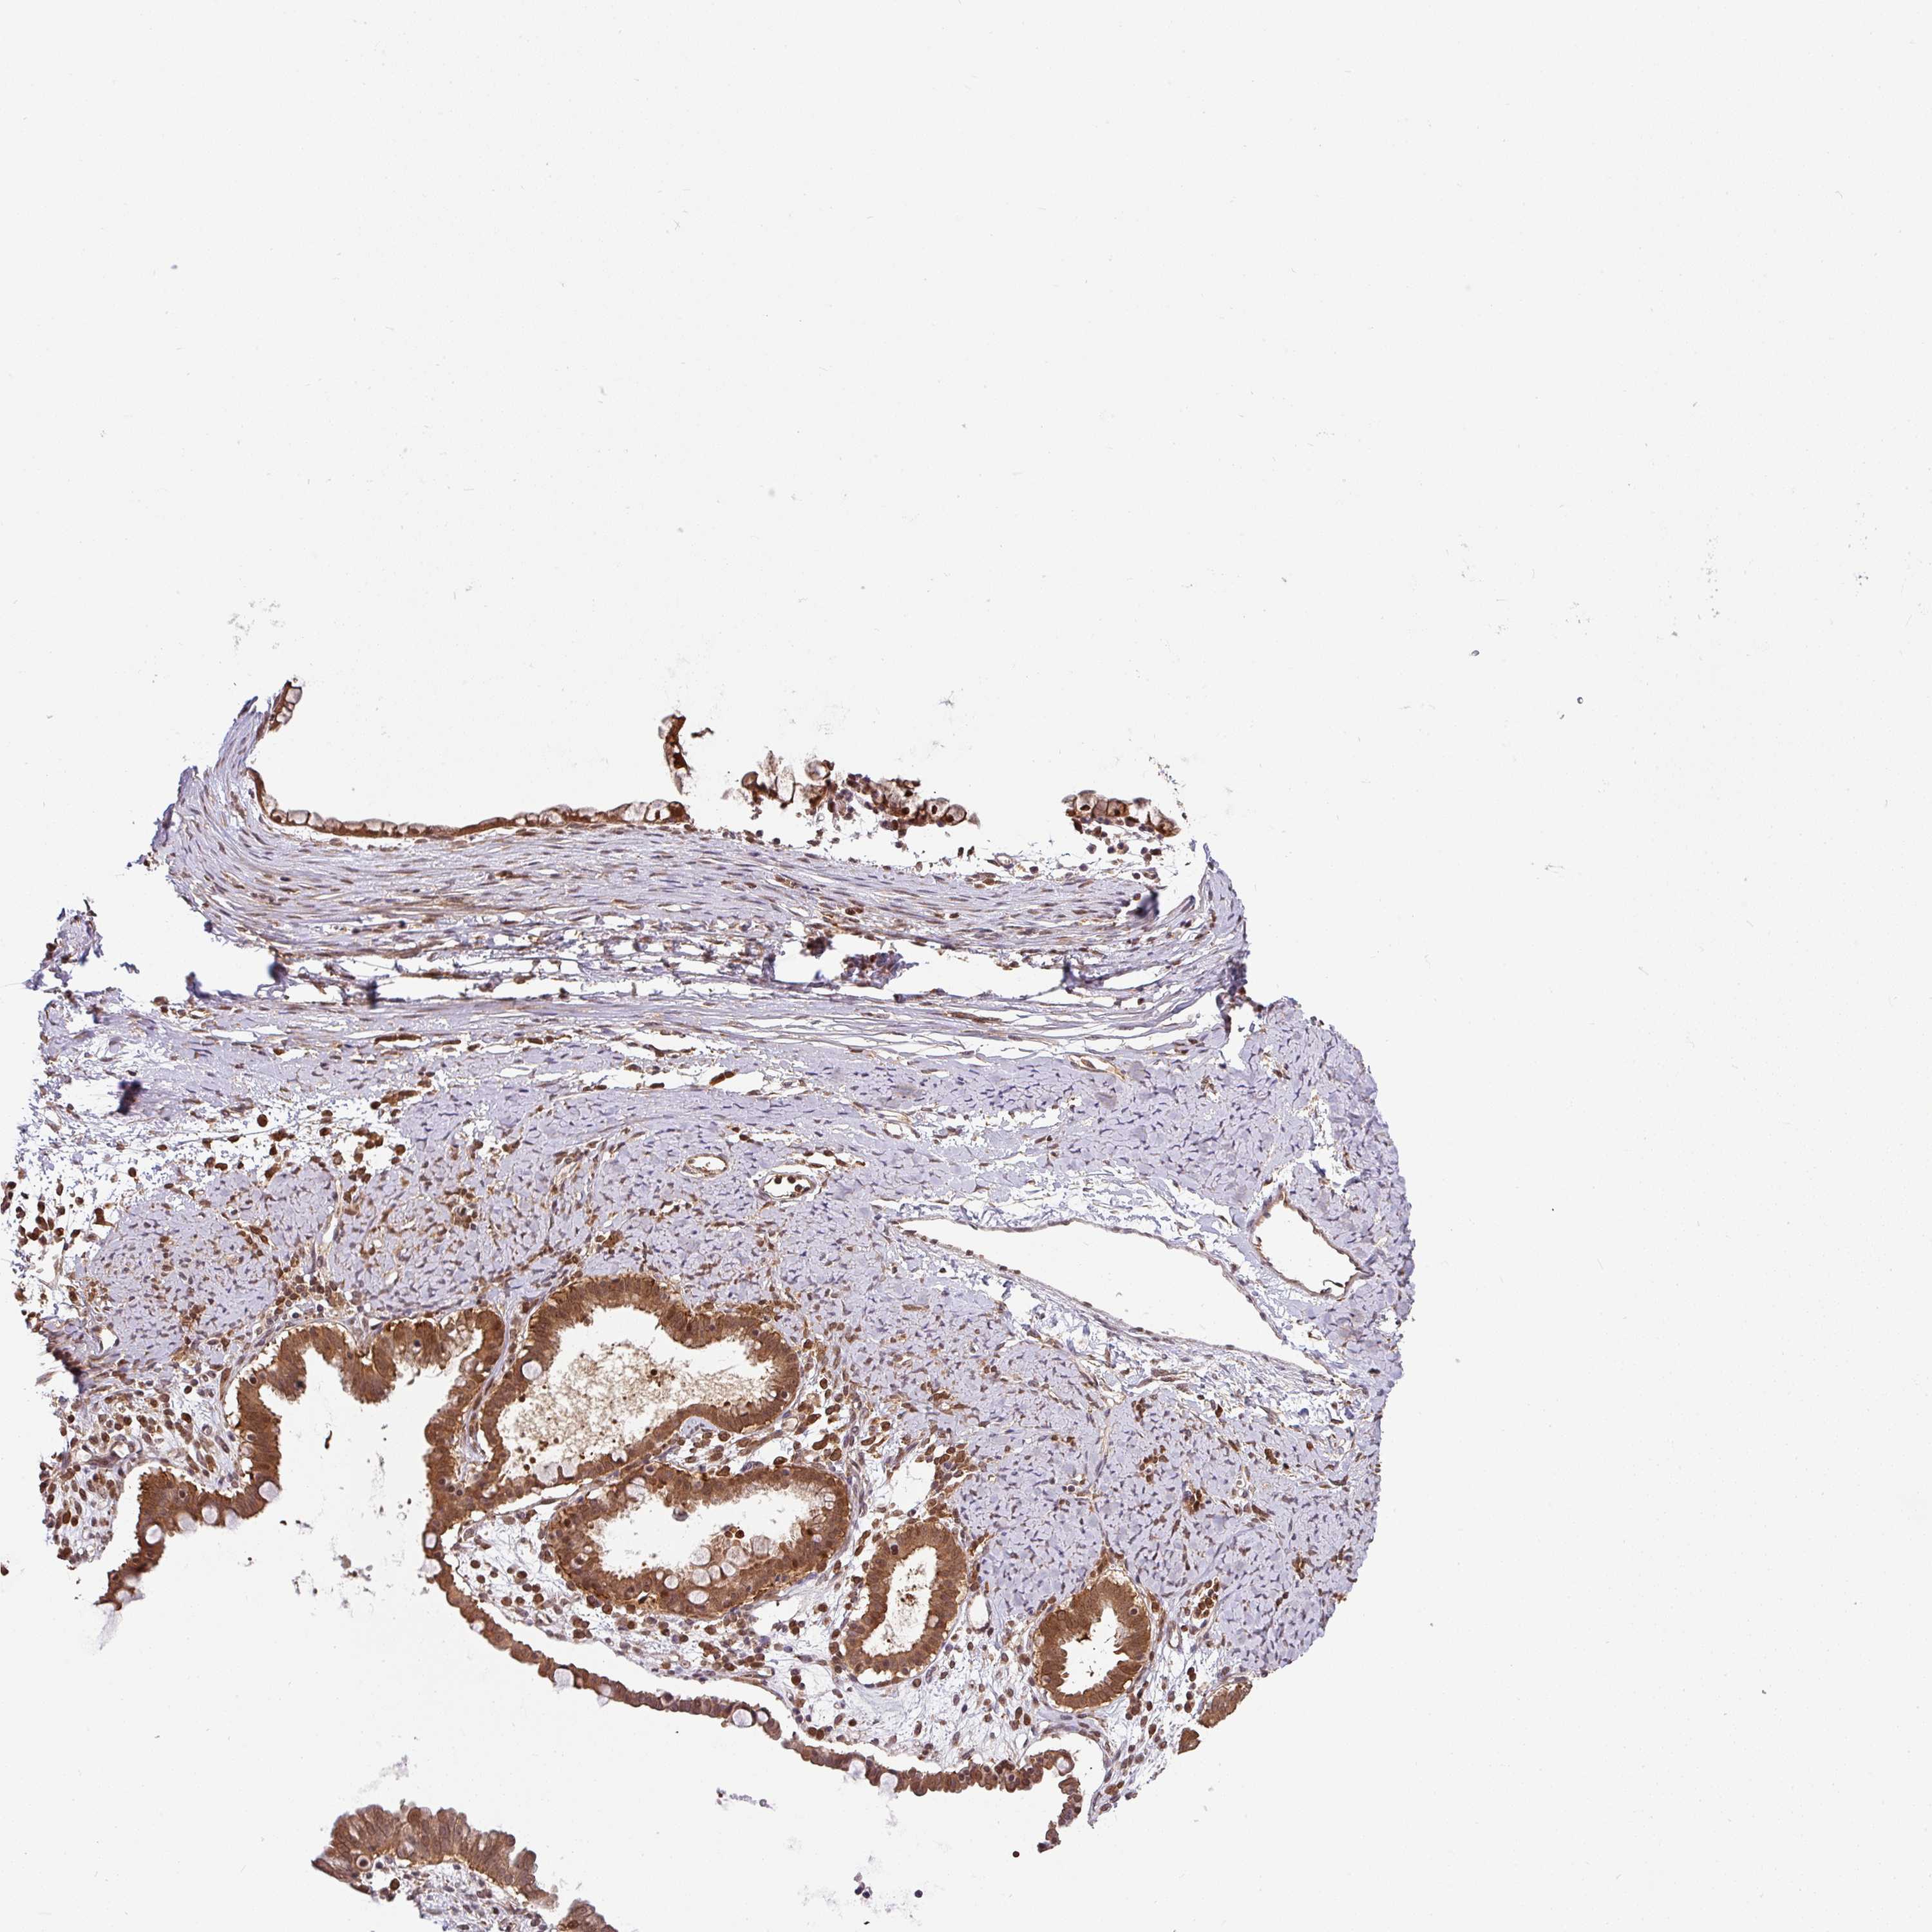

OVARIAN CANCER - Protein expressioni

A mouse-over function shows sample information and annotation data. Click on an image to view it in a full screen mode. Samples can be filtered based on level of antibody staining by selecting one or several of the following categories: high, medium, low and not detected. The assay and annotation is described here.

Note that samples used for immunohistochemistry by the Human Protein Atlas do not correspond to samples in the TCGA dataset.

Antibody stainingi

Antibody staining in the annotated cell types in the current human tissue is reported as not detected, low, medium, or high, based on conventional immunohistochemistry profiling in selected tissues. This score is based on the combination of the staining intensity and fraction of stained cells.

Each image is clickable and will lead to virtual microscopy that enables deeper exploration of all samples and also displays staining intensity scores, fraction scores and subcellular localization as well as patient and tissue information for each sample.

Antibody HPA049911

Antibody CAB010161

Cystadenocarcinoma, serous, NOS

Cystadenocarcinoma, mucinous, NOS

Adenocarcinoma, NOS

Carcinoma, endometroid

Carcinoma, NOS